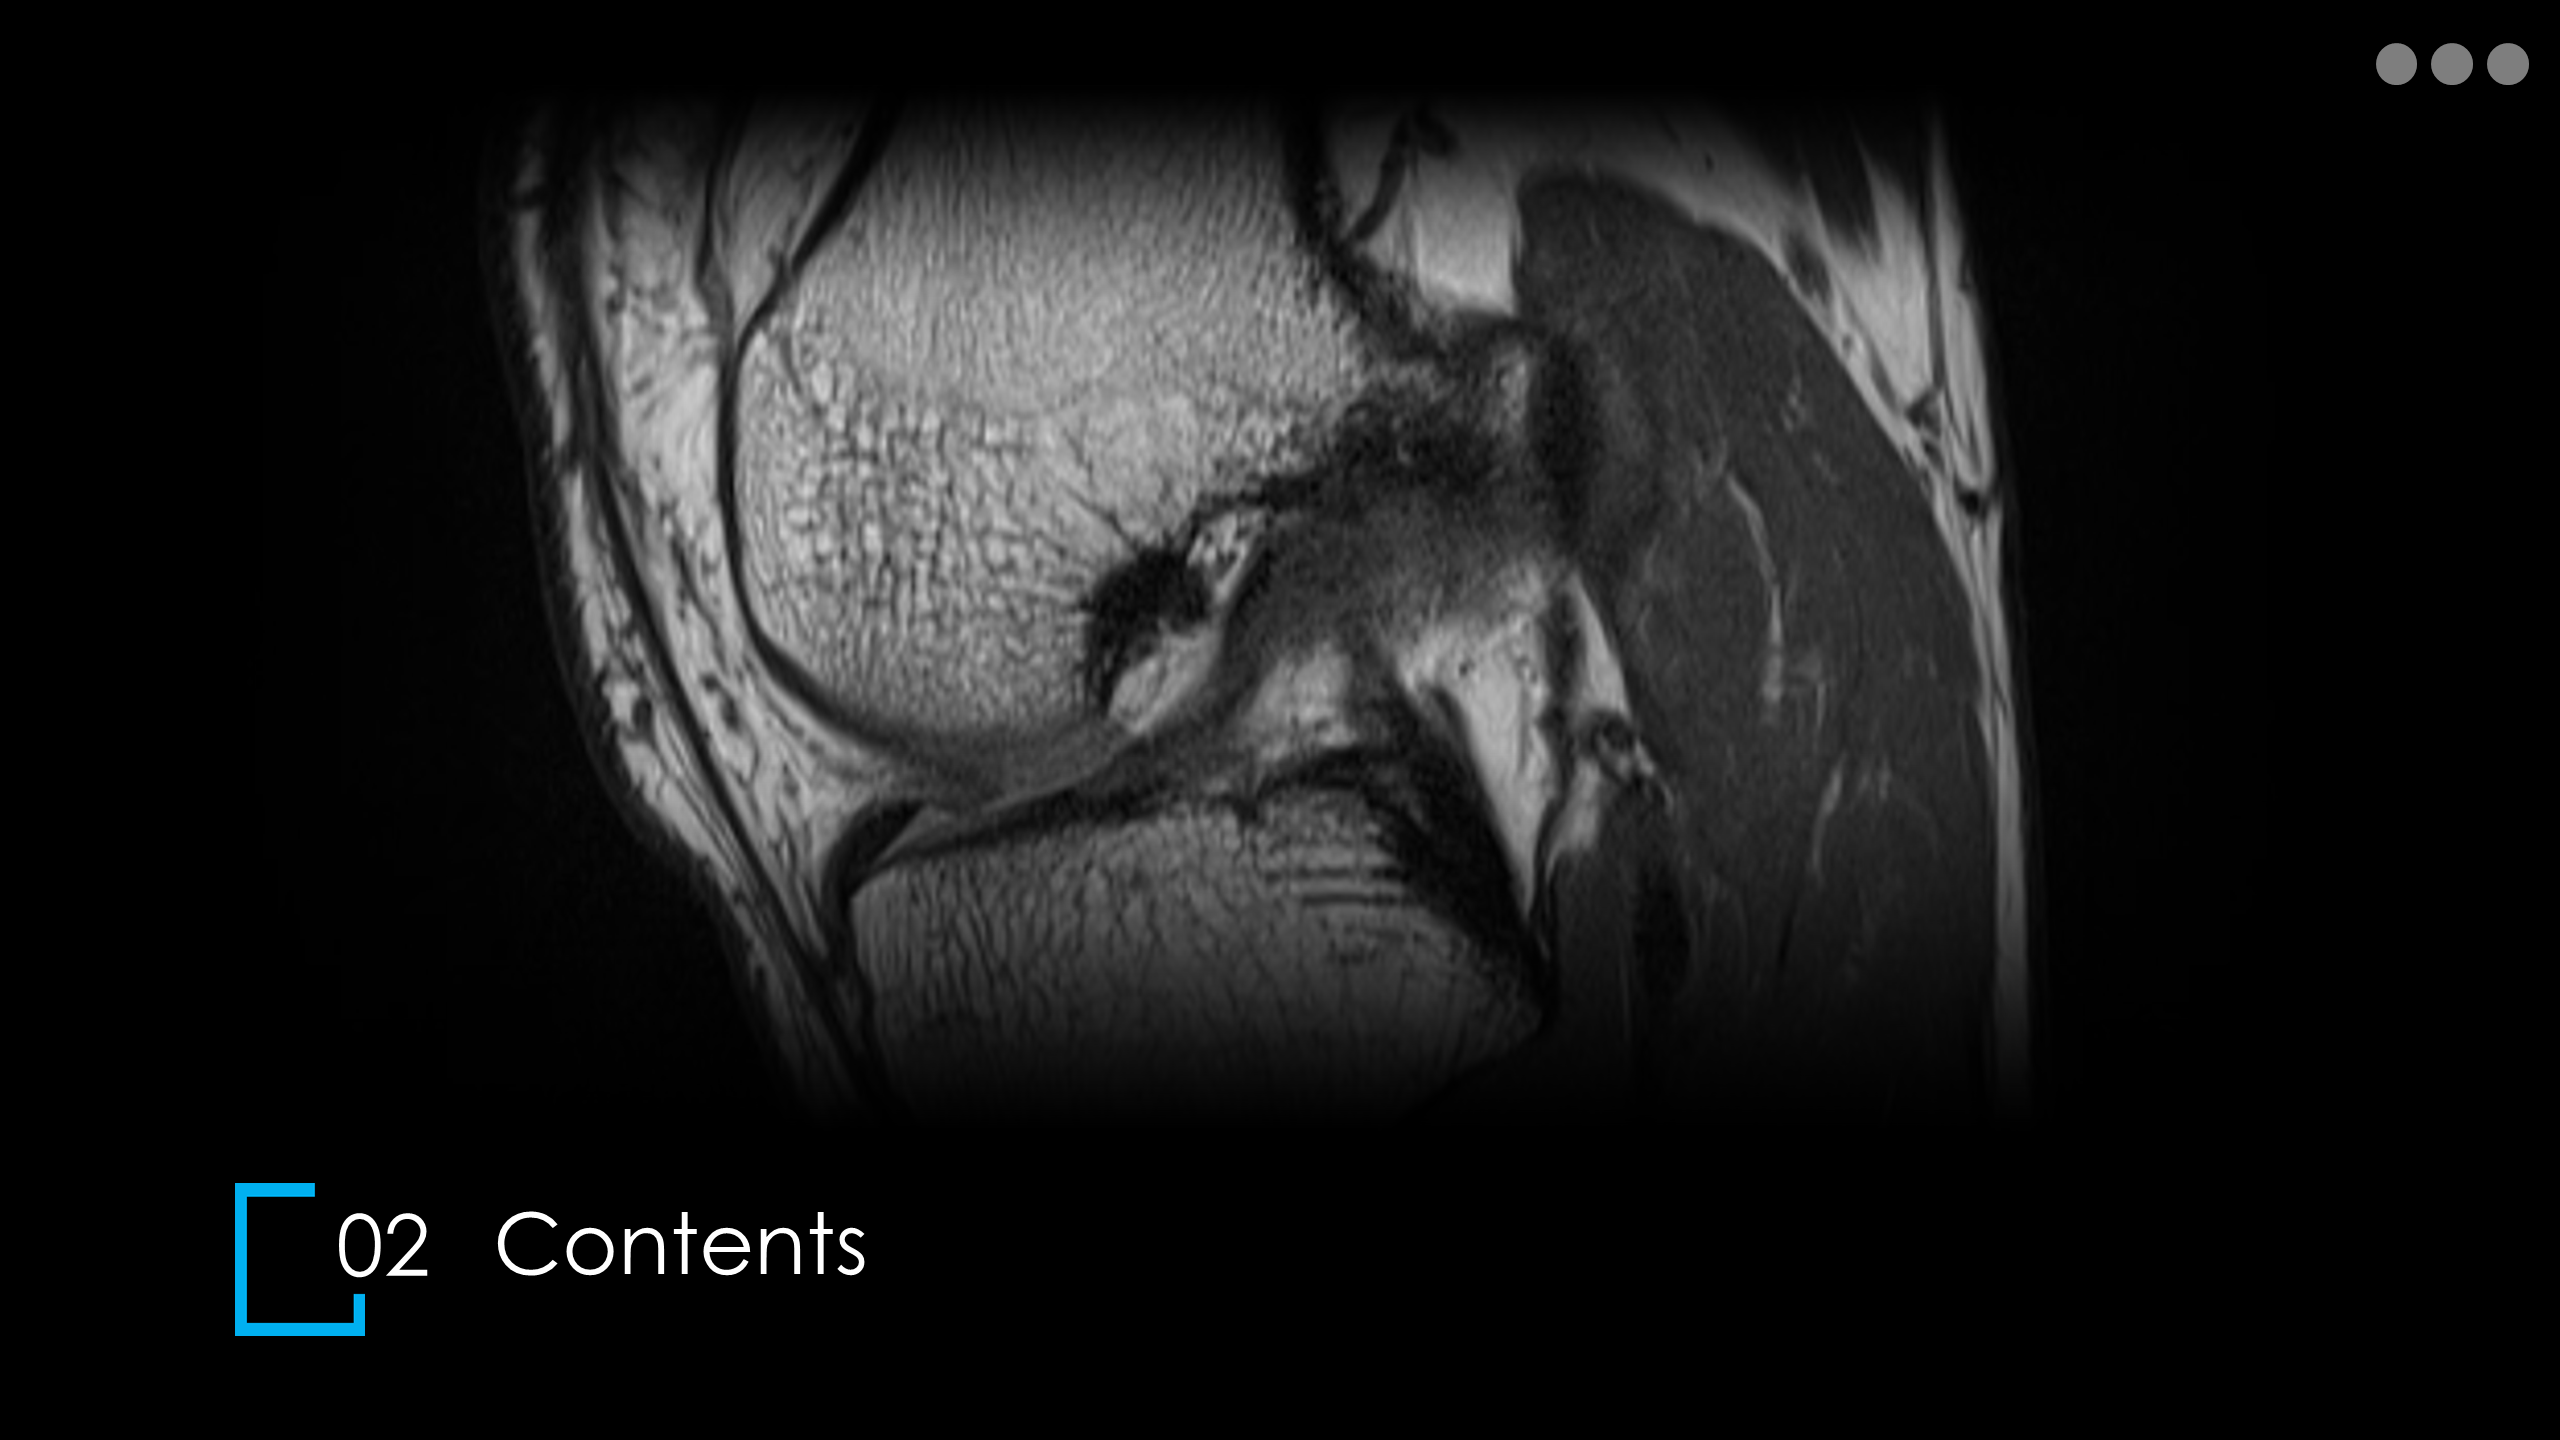

주제: The Knee MRI Approach

강사: 신민섭

아래의 Normal Knee MR Anatomy를 숙지하고 오셔야, 강의에 어려움이 없습니다.